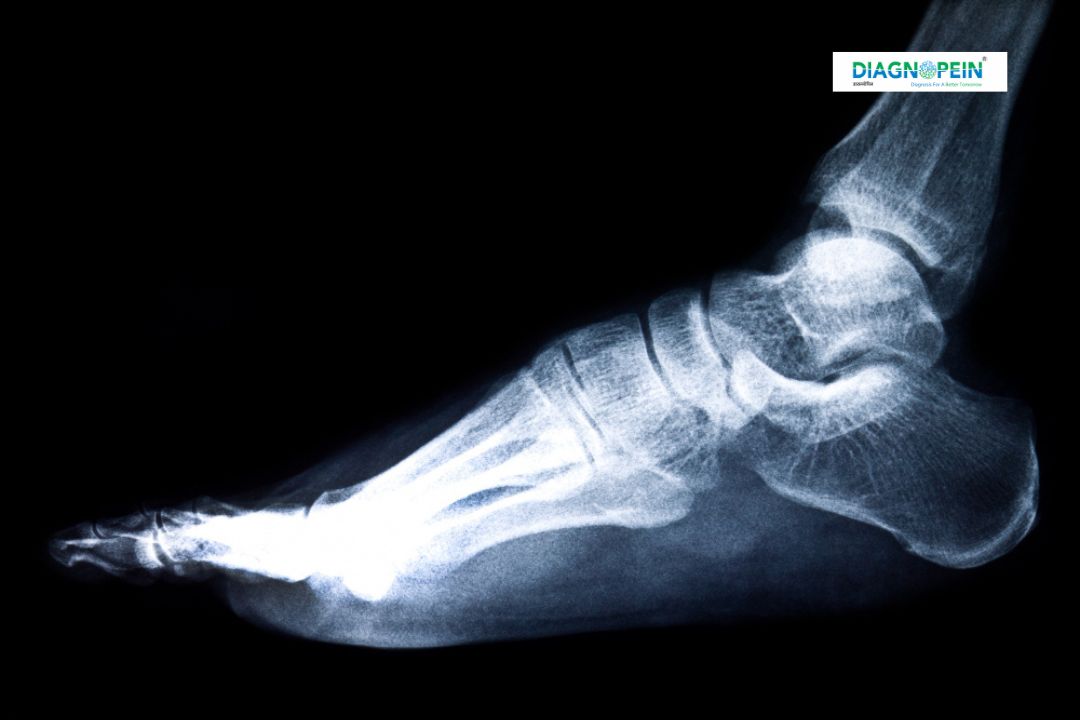

The X-Ray Left Ankle Joint AP/LAT Views is a diagnostic imaging test that provides detailed images of the bones, joints, and soft tissues around the left ankle. The AP (Anteroposterior) and Lateral (LAT) views help doctors evaluate the ankle from multiple angles, making it easier to detect fractures, dislocations, bone alignment, joint spacing, or signs of arthritis.

2. Positioning: The technician will position your left foot on the X-ray plate — one shot will be taken from the front (AP view) and another from the side (LAT view).

5. Result Interpretation: A radiologist examines the images to detect any fractures, joint space narrowing, or alignment deformities.